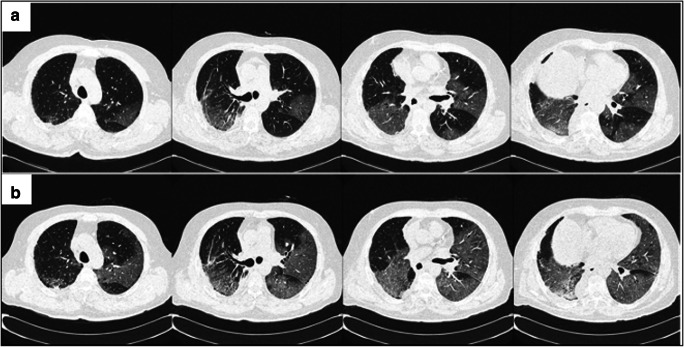

A 61-year-old male smoker was admitted to our hospital for surgical treatment of a lung adenocarcinoma, diagnosed on biopsy. His clinical history was positive for a MALT lymphoma diagnosed 6 months before, with complete remission after therapy. According to pre-operatory imaging, obtained 3 weeks before surgery, the lesion was localized in the right inferior lobe, measured 2 cm and showed a solid appearance. There were no ground glass opacities. At admission, the patient was in good general condition, afebrile. A thoracoscopic lobectomy with lymph node dissection (stations 2, 4, 7, 8, 9, and 10) was performed, without intraoperative complications. After surgery, the patient developed progressive lymphopenia (with values ranging between 920 and 340 lymphocytes/μL from the first to the fifth post-operative day) and, on the scheduled date for discharge, had an episode of fever (38 °C) in the absence of respiratory symptoms. Thus, his antibiotic therapy was changed, with no improvement. A pharyngeal swab PCR test was performed, which confirmed the suspicion of SARS-CoV-2 infection. The patient was immediately transferred to the isolation ward where he developed cough, dyspnea, fatigue, and high fever (38–39 °C). SpO2 was stable between 96 and 98%. Both white blood cells (2570/μL) and lymphocytes counts were low (280/μL). A chest CT scan showed post-resection changes and bilateral, peripheral, and ill-defined ground-glass opacities, mainly involving the lower lobe, consistent with Covid-19 pneumonia (Fig. 1a).

Fig. 1.

High-resolution CT scans performed one (a) and two (b) weeks after surgery, respectively show ground glass bilateral opacities, enlarging with time, with the additional finding of areas of consolidation

Since oxygen saturation had dropped to 35%, he received supplemental oxygen through a CPAP mask. On a second CT scan, performed 1 week later, the ground-glass opacities were enlarged, with areas of consolidation (Fig. 1b). He received a therapy based on antibiotics (meropenem and bactrim), antiviral drugs (acyclovir and darunavir), and on two recently approved experimental drugs for SARS-CoV-2 infection: tocilizumab (commonly used for the therapy of rheumatoid arthritis) and chloroquine hydrate (a common antimalarial drug), with an improvement of his conditions and clinical remission in the following weeks.